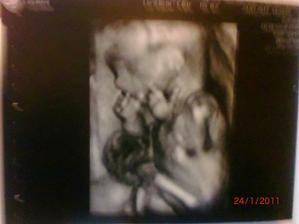

24.1.2011 - dozvěděli jsme se,že čekáme druhýho chlapečka - Matyáška

4.2.2011 - Velký utz,potvrzen chlapeček,vše je v pořádku,jen je Matýsek moc dole a tak byl problém ho změřit..